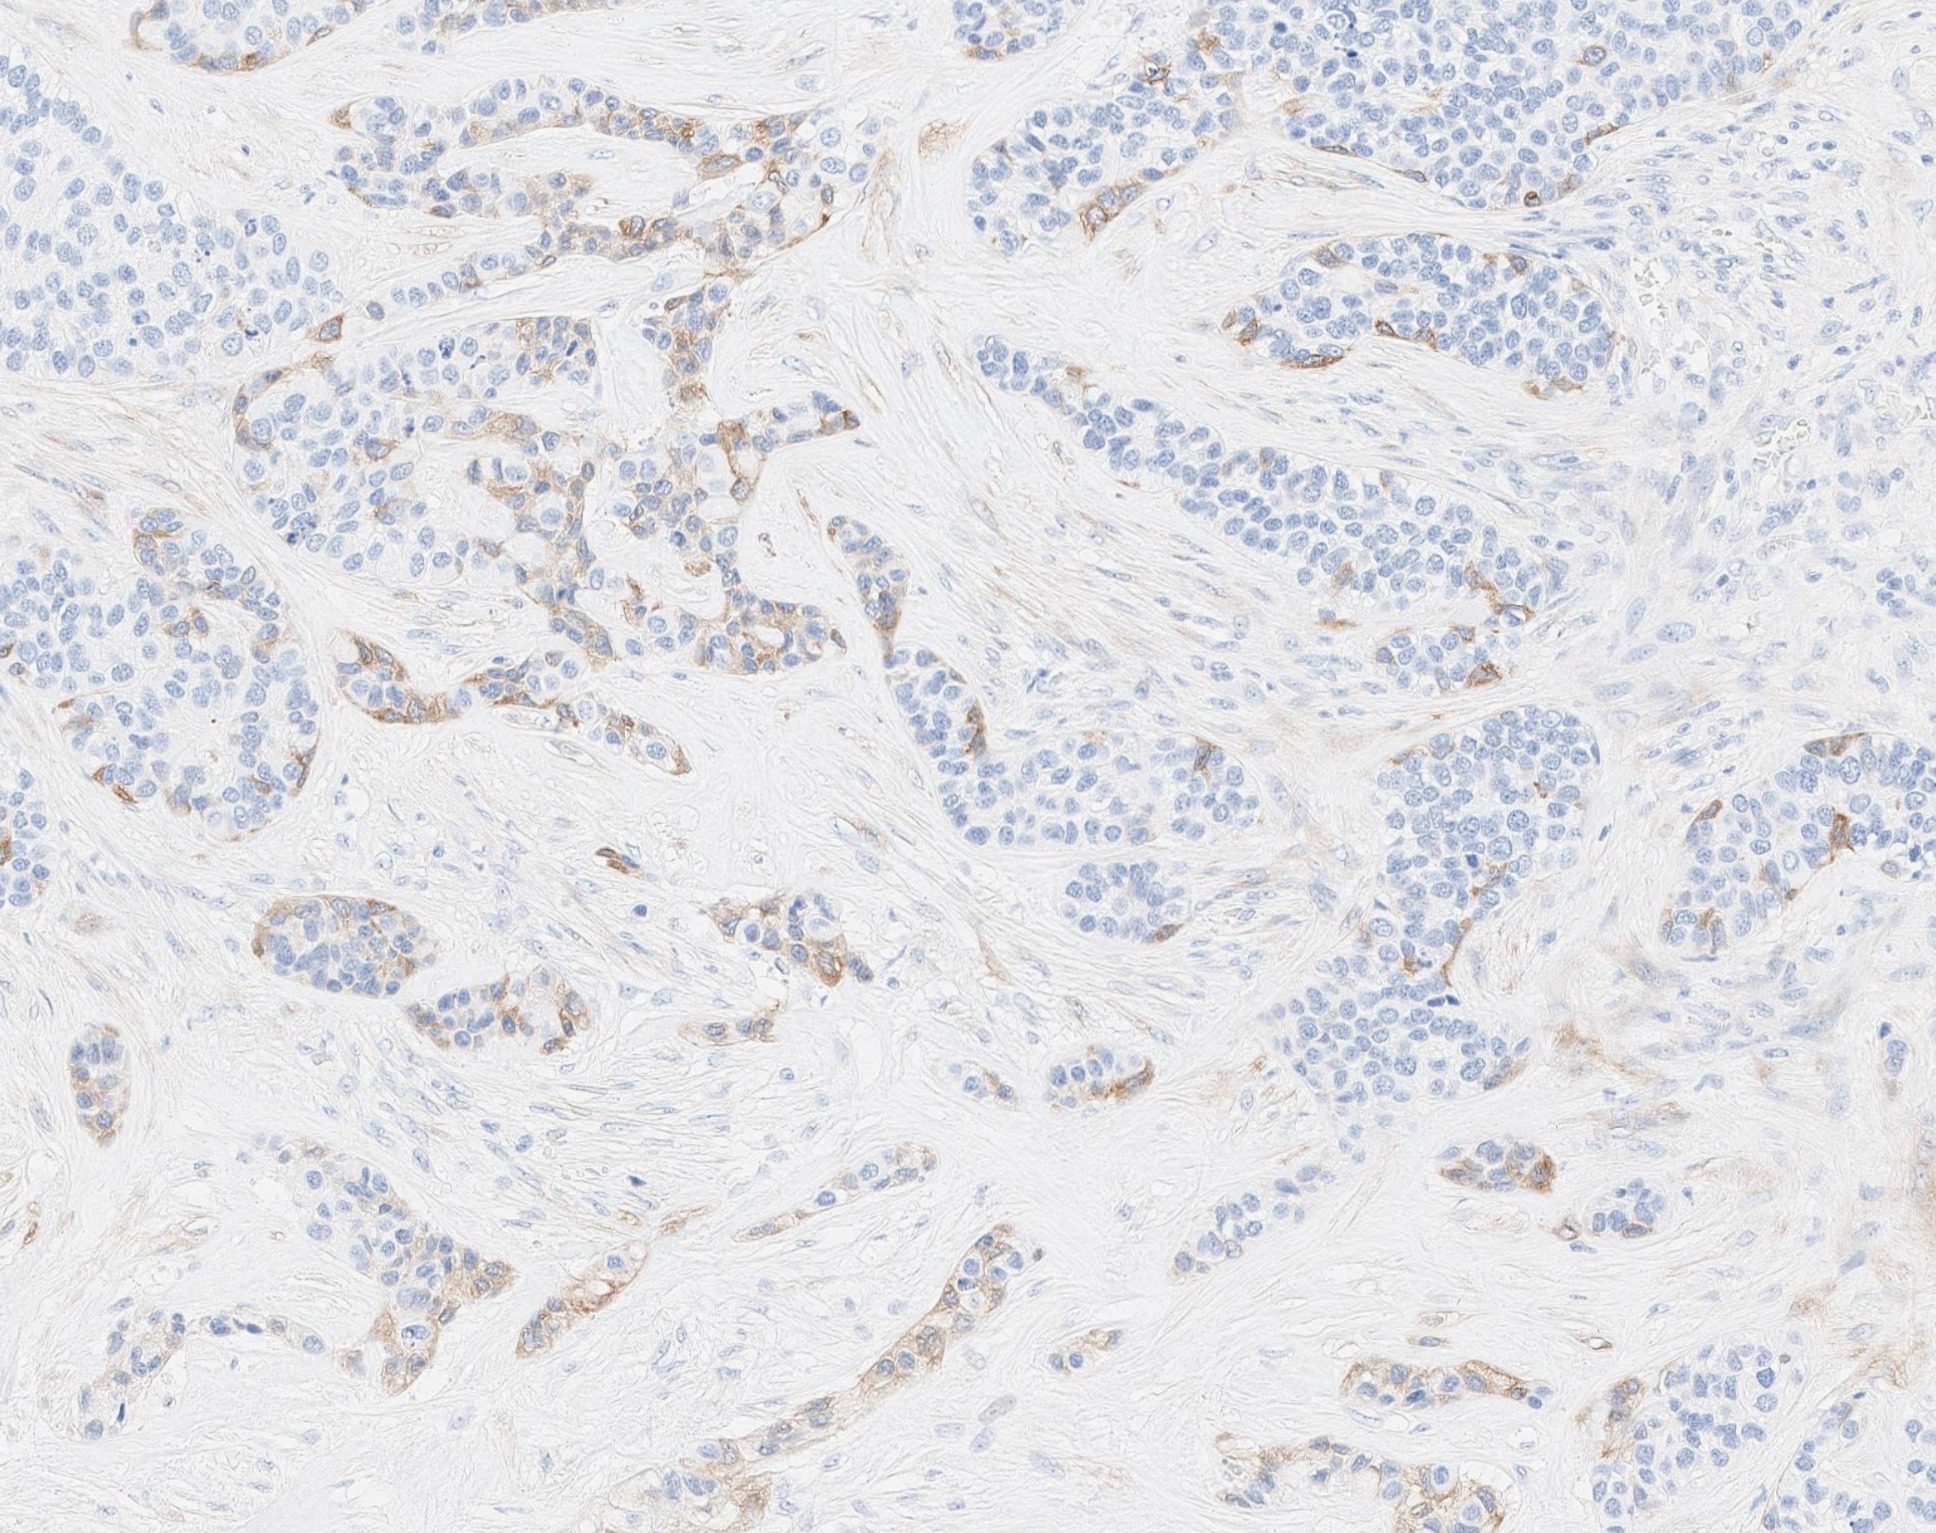

Microscopic (histologic) images

Contributed by Abeer Salama, M.D. and Bin Xu, M.D., Ph.D.

Positive stains

Negative stains

- Melanocytic markers, such as HMB45 and MelanA (Surg Pathol Clin 2021;14:67)

- Comment: The tumor shows a mitotic index of 8 per 10 high power fields. Tumor necrosis is noted. Immunohistochemistry studies show that the tumor is positive for S100, calponin and CAM5.2, whereas negative for HMB45. The morphologic and immunohistochemical features are most consistent with myoepithelial carcinoma.